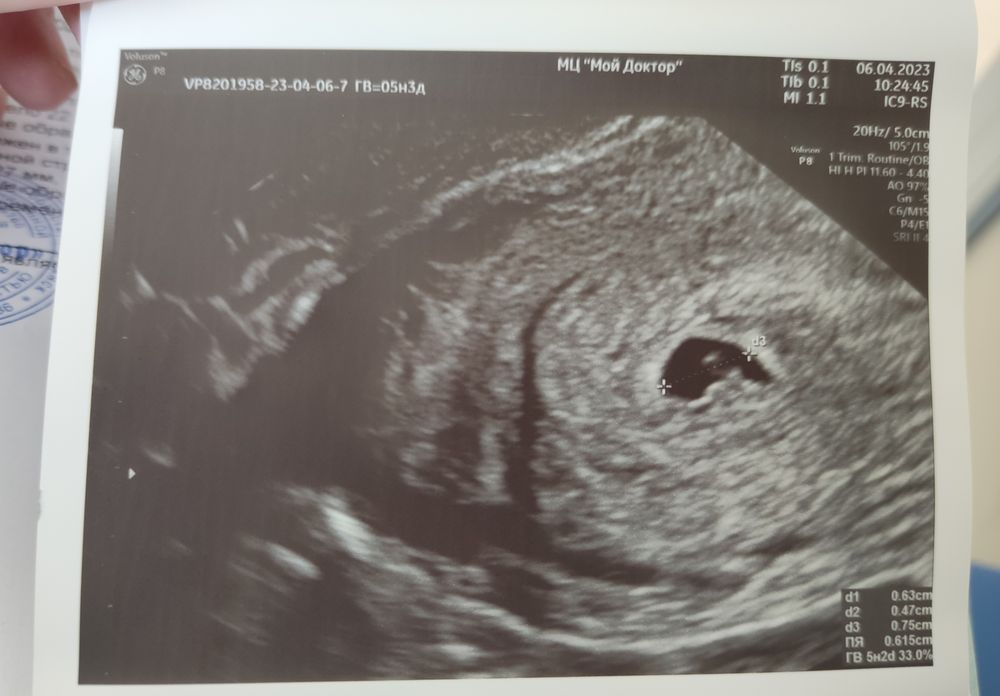

Нас нашли в матке, ПЯ соотвествует сроку! ✨

Изображение

Сердцебиения ❤ пока нет, но я и не переживаю по этому поводу, с сыном оно уже было, так как ХГЧ был приличный, а